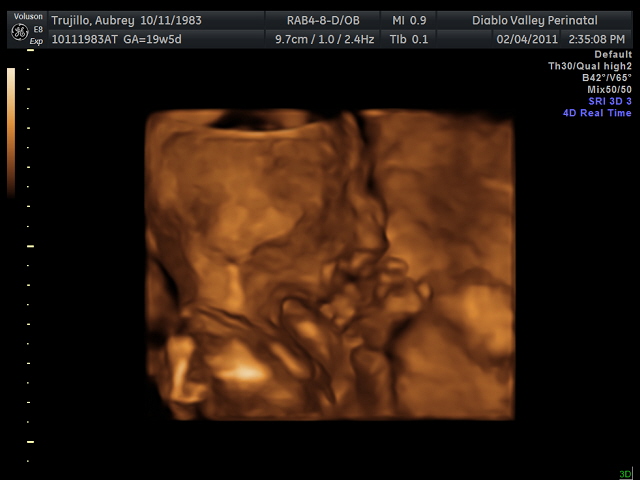

20 weeks - profile20 weeks - Profile again20 weeks - Right foot!20 weeks - sucking thumb!!!!20 weeks - hand near face20 weeks - flexing his bony arms!20 weeks - hiding from mommy and daddy!20 weeks - it's a boy!33 weeks - 3D!33 weeks - 3D!33 weeks - 3D!